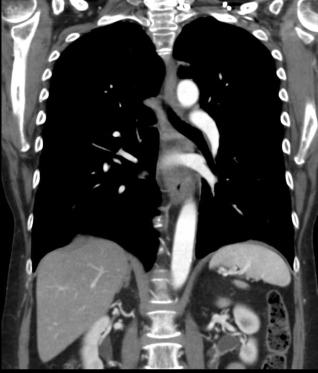

Un autre cas de cancer epidermoide du

1/3 moyen de oesophage avec metastase ganglionaire

pulmonaire . Bilan pre-therapeutique .

- Image TDM fenetre mediastinal en coupe

coronal ( frontale) et en coupe axiale a

traverse la tumeur . Image du tumeur de

oesophage avec extention locaux aortique et au

ganglions pulmonaires